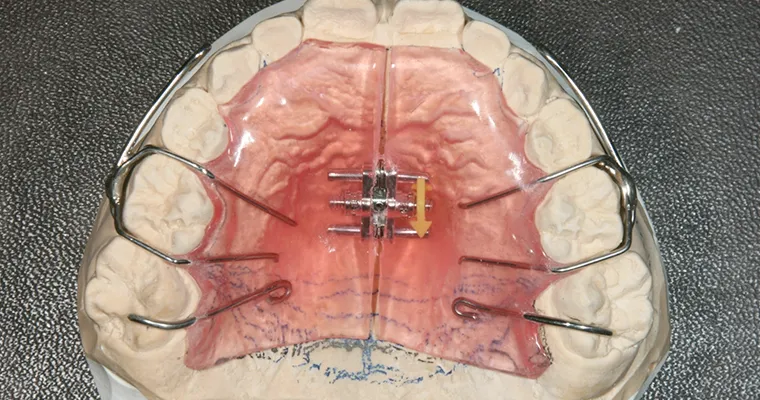

使用矯正装置 上

使用矯正装置 下

| 主訴 | 歯並びが悪い 乳歯と永久歯が重なっている 歯がまっすぐはえてこない |

|---|---|

| 治療期間 | 6-7ヶ月 |

| 治療費 | 440,000円(税込) ※調整、器具、治療後にお渡しするEFLine(矯正後の後戻りを防ぐ器具)も全て込みでの金額となっております。 |

| 治療内容 | 拡大床矯正 EF Lineで筋機能療法 |